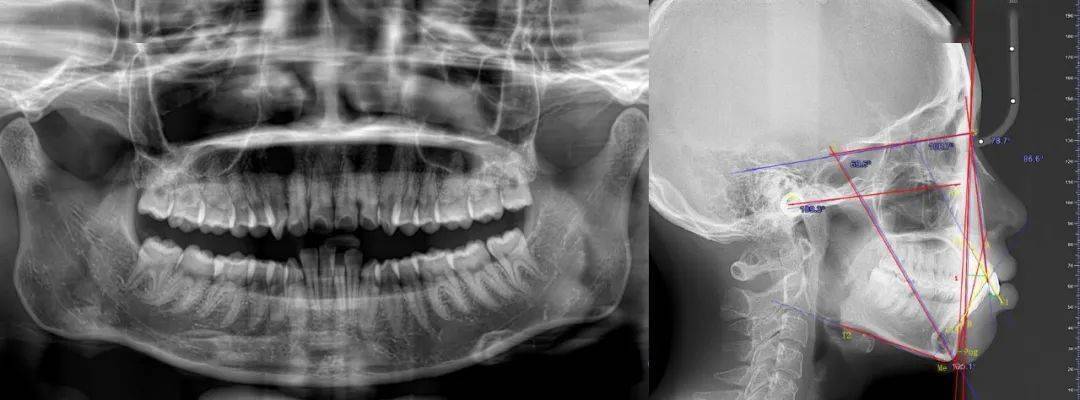

头颅侧位片的解读依赖角度、距离等客观测量指标,以下为核心参数及其临床意义:

| 指标名称 | 定义 | 正常值范围 | 临床意义 |

|---|---|---|---|

| SNA角 | 蝶鞍中心-鼻根点-上齿槽座点角 | 82°±4° | 反映上颌骨相对颅骨位置,>84°提示上颌前突 |

| SNB角 | 蝶鞍中心-鼻根点-下齿槽座点角 | 80°±4° | 反映下颌骨相对颅骨位置,<76°提示下颌后缩 |

| ANB角 | SNA角与SNB角差值(SNA-SNB) | 2°±2° | 上下颌骨相对关系,>4°上颌前突或下颌后缩 |

| 下颌平面角(MP-FH) | 下颌平面(下颌下缘切线)与FH平面夹角 | 32°±5° | 垂直生长型,>35°高角(易露龈笑),<28°低角 |

| 上中切牙角(UI-SN) | 上中切牙长轴与SN平面(蝶鞍-鼻根点)夹角 | 105°±6° | 上前牙倾斜度,>111°唇倾(易露龈),<99°舌倾 |

| 覆盖 | 上中切牙切缘至下中切牙唇面水平距离 | 2-4mm | 水平向错颌,>4mm深覆盖,<0mm反颌 |

| 覆合 | 上中切牙切缘覆盖下中切牙冠长的比例 | 1/3-1/2 | 垂直向错颌,>1/2深覆合,<0°开颌 |